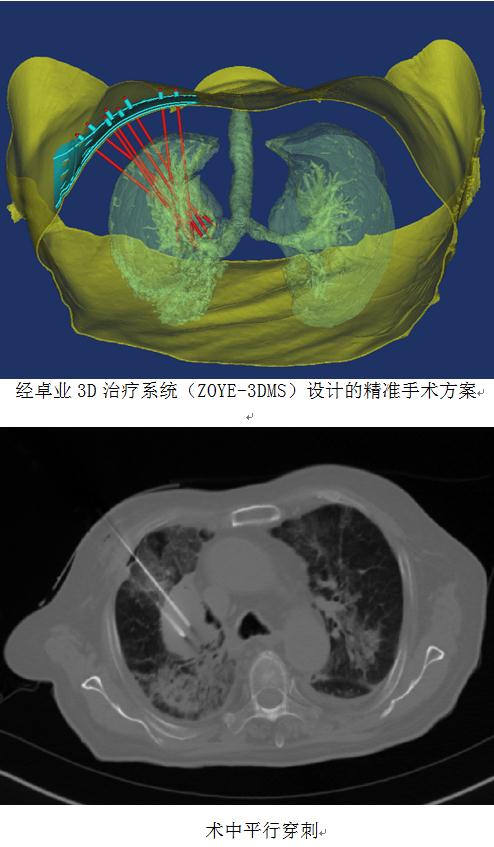

放射科宓主任医疗团队使用卓业科技的3D治疗系统(ZOYE-3DMS V1.0)设计出符合患者病情的个体化穿刺方案,并在3D打印联合模板的精准定位引导下,通过穿刺针道的均匀分布和放射剂量合理选择,为患者实施的手术达到了非常理想的治疗效果。

3D打印技术又叫做快速成型技术,可以在短时间内完成原型设计的制造,这在视时间为生命的医疗领域有着天然的契合。山东卓业电子科技有限公司自主研发的3D治疗系统(ZOYE-3DMS V1.0)是涵盖了模板设计、影像检视、自动三维数据建模、3D打印、数据传输和数据安全等功能一体化的先进系统。该系统为临床医生设计手术方案、提高治疗效果等提供了强有力在支撑。